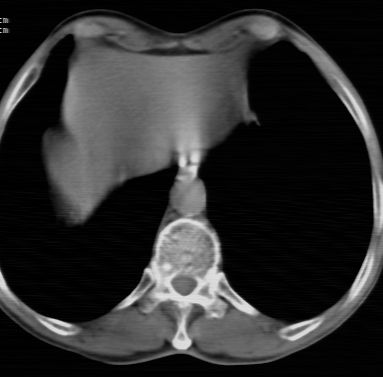

标题: CT24783:m71,既往肺心病史3年,现咳嗽,憋喘。 [打印本页]

标题: CT24783:m71,既往肺心病史3年,现咳嗽,憋喘。

1)左肺上叶周围型肺癌可能。2)两肺全小叶型肺气肿。